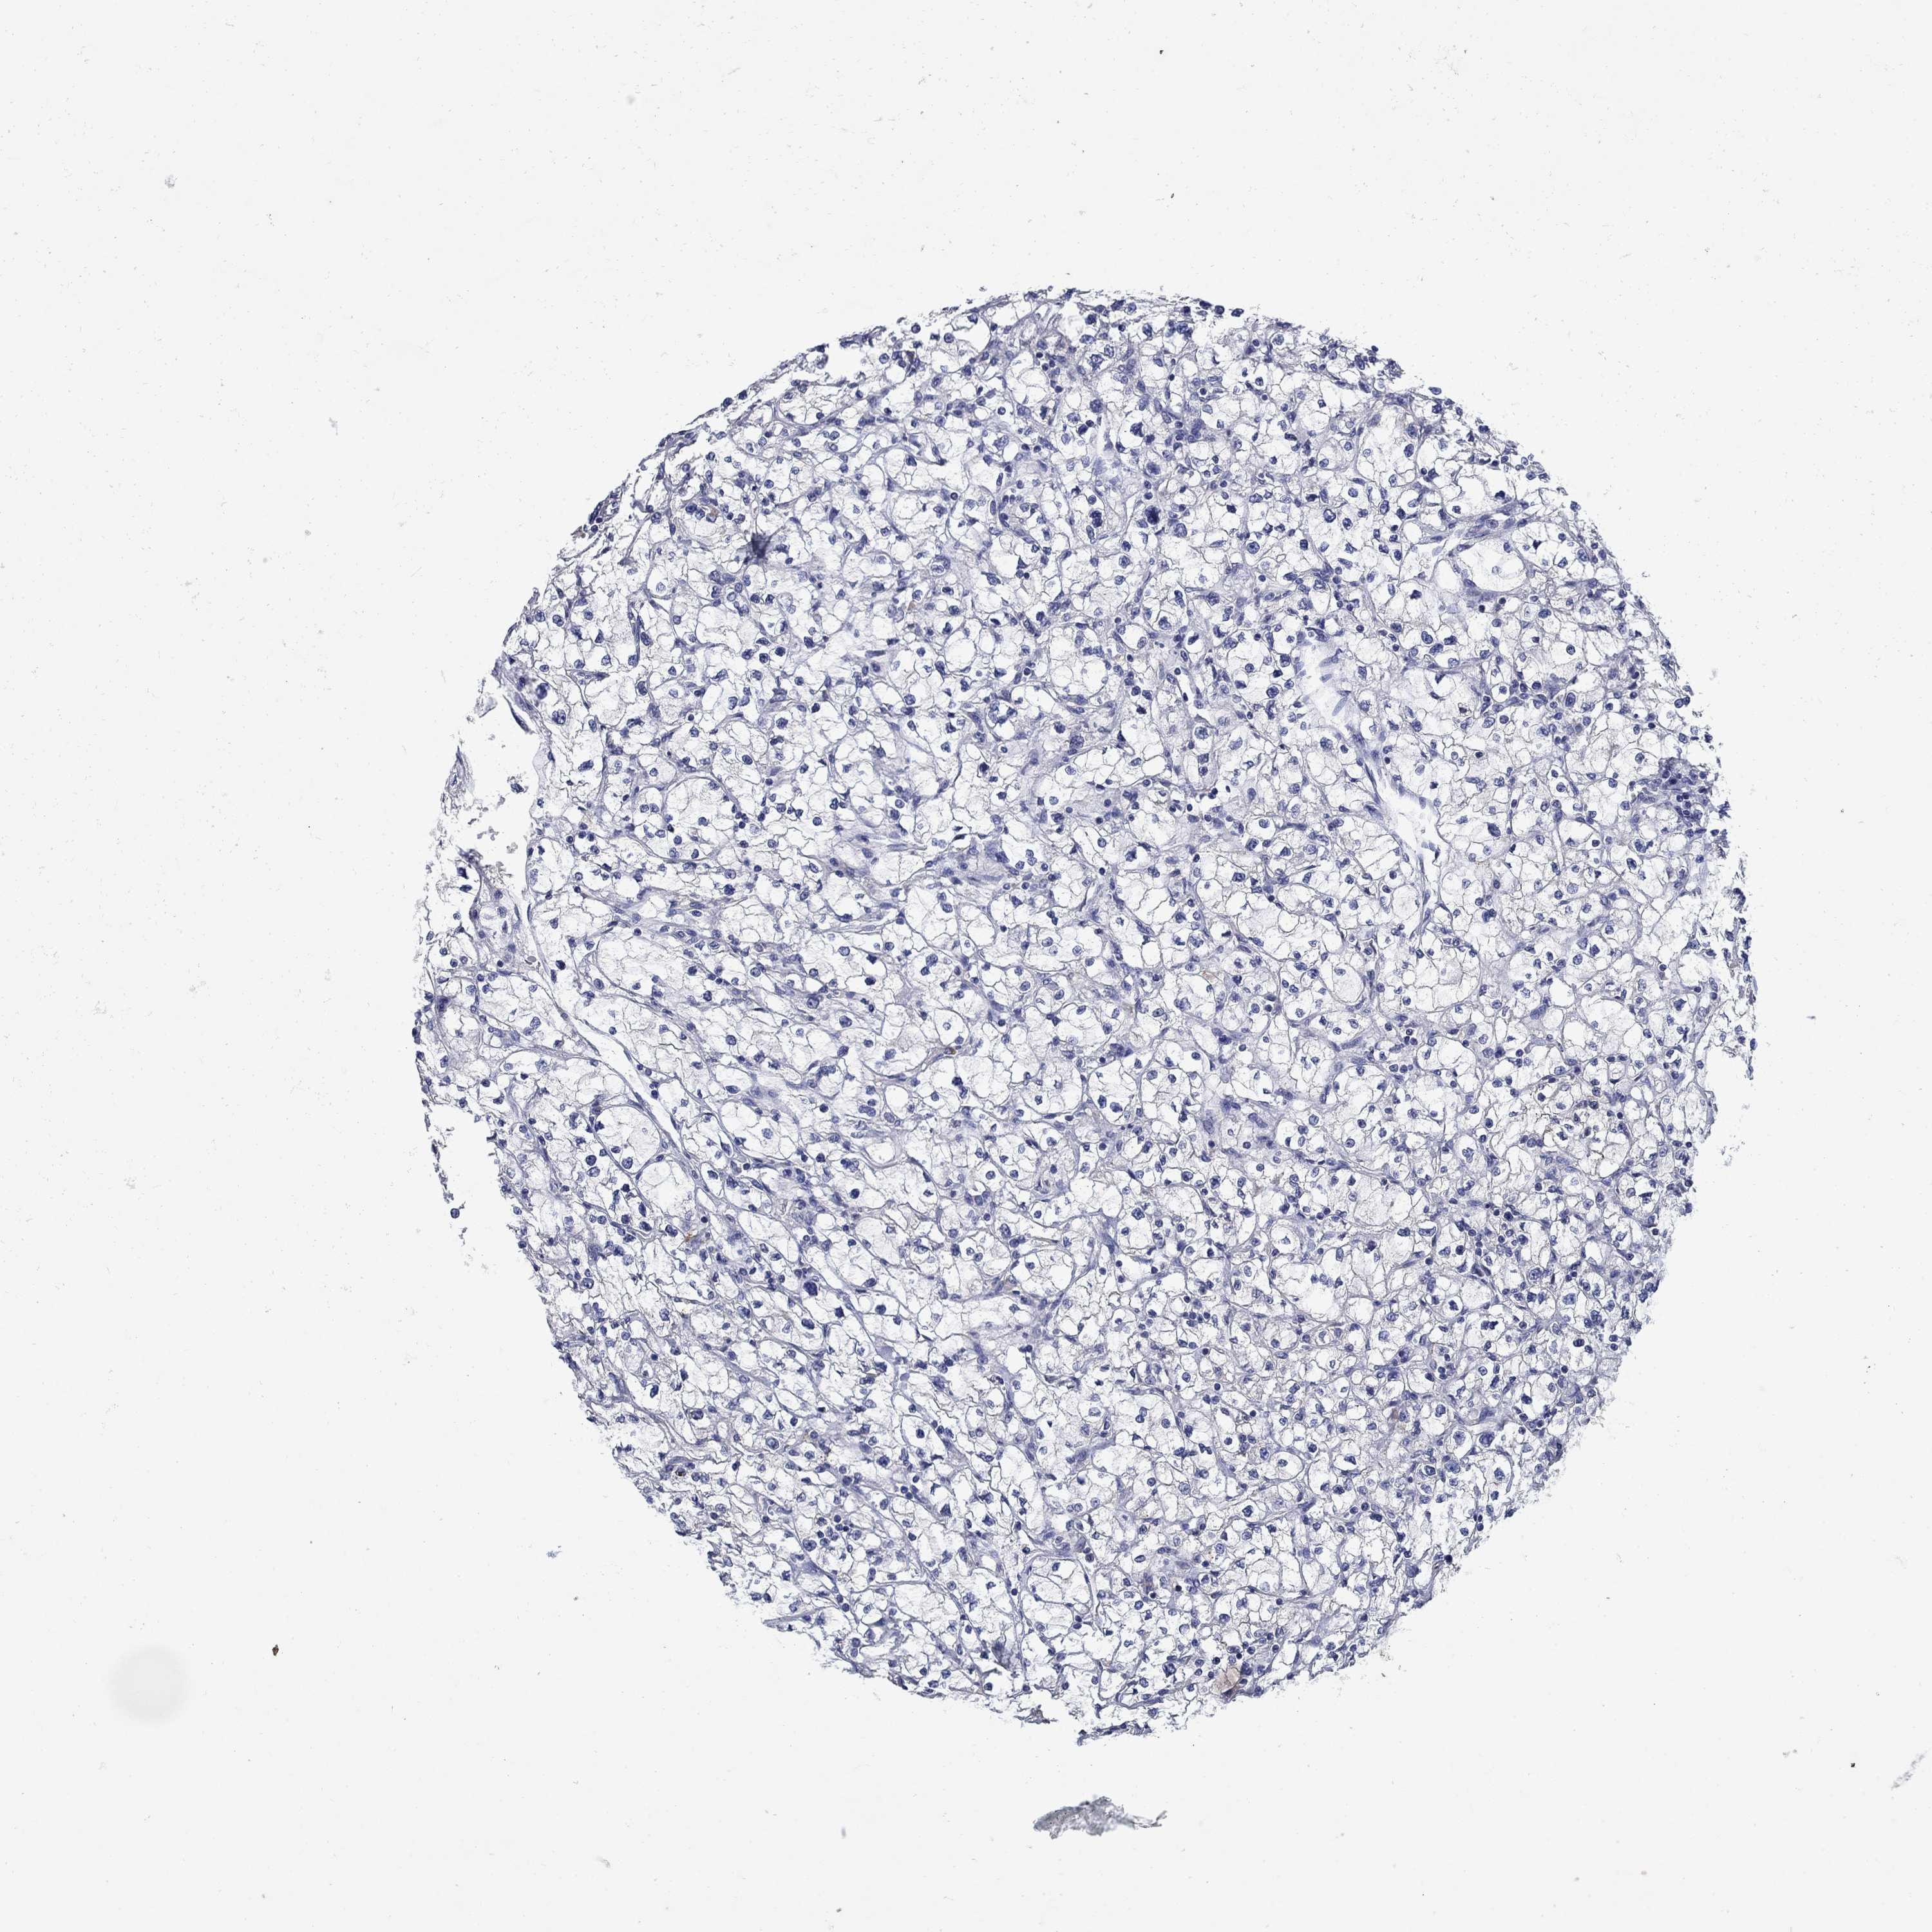

Average pTPM 0.9

Number of samples 521